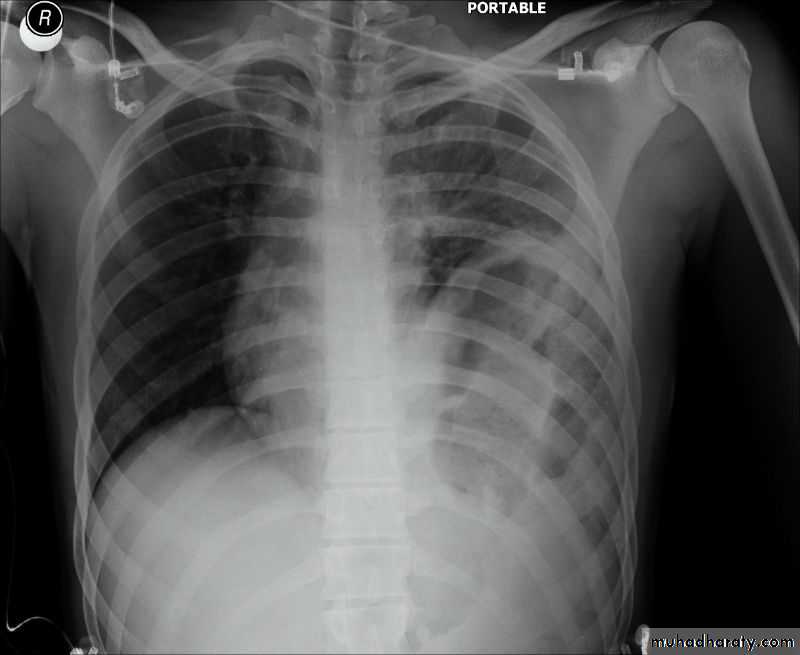

Patient with fever, rigor and dyspnea